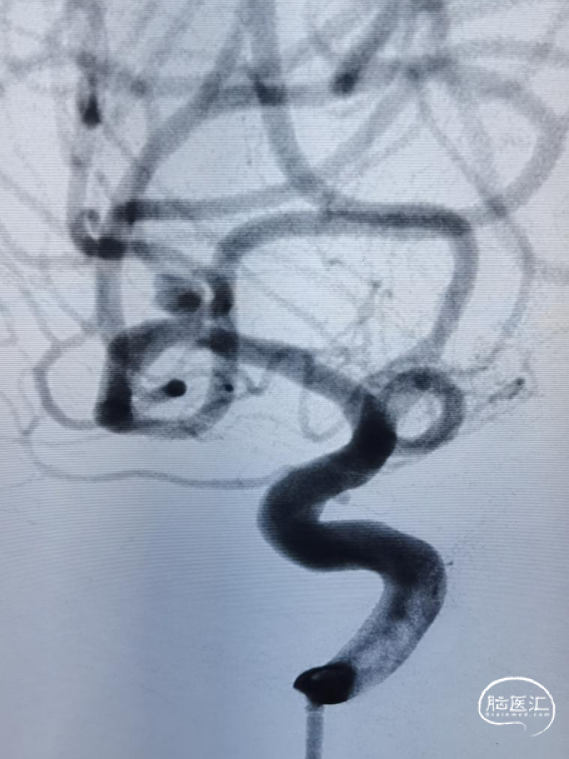

术中全身肝素化,6F DA导引导管到达颈内动脉C1段远端,根据3D图像选取工作角度造影充分暴露载瘤动脉、瘤颈、动脉瘤长径。

使用SL-10 微导管在Synchro 微导丝引导下分别进入载瘤动脉及动脉瘤腔内。

采取半释放法于上干释放3*21mm Altas支架1枚,同时于动脉瘤内填塞弹簧圈至致密。

最后全释放支架,序贯撤出微导管,造影可见支架打开完全、贴壁完美,载瘤动脉角度变化小,管腔通畅,动脉瘤Raymond 1级栓塞。